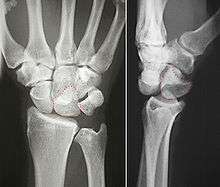

![]() Left hand anterior view (palmar view). Lunate bone shown in red. | |

The lunate bone (semilunar bone) is a carpal bone in the human hand. It is distinguished by its deep concavity and crescentic outline. It is situated in the center of the proximal row carpal bones, which lie between the ulna and radius and the hand. The lunate carpal bone is situated between the lateral scaphoid bone and medial triquetral bone.

The lunate is a crescent-shaped carpal bone found within the hand. The lunate is found within the proximal row of carpal bones. Proximally, it abuts the radius. Laterally, it articulates with the scaphoid, medially with the triquetral, and distally with the capitate. The lunate also articulates on its distal and medial surface with the hamate bone.[1]:708[2]

The proximal surface of the lunate bone is smooth and convex, articulating with the radius. The lateral surface is flat and narrow, with a crescentic facet for articulation with the scaphoid. The medial surface possesses a smooth and quadrilateral facet for articulation with the triquetral. The palmar surface is rough, as is the dorsal surface. The dorsal surface is broad and rounded. The distal surface of the bone is deep and concave.[3]